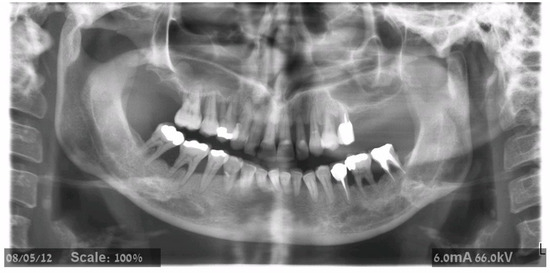

- Cone-beam tomographic (CBCT) examination was obtained before surgery.